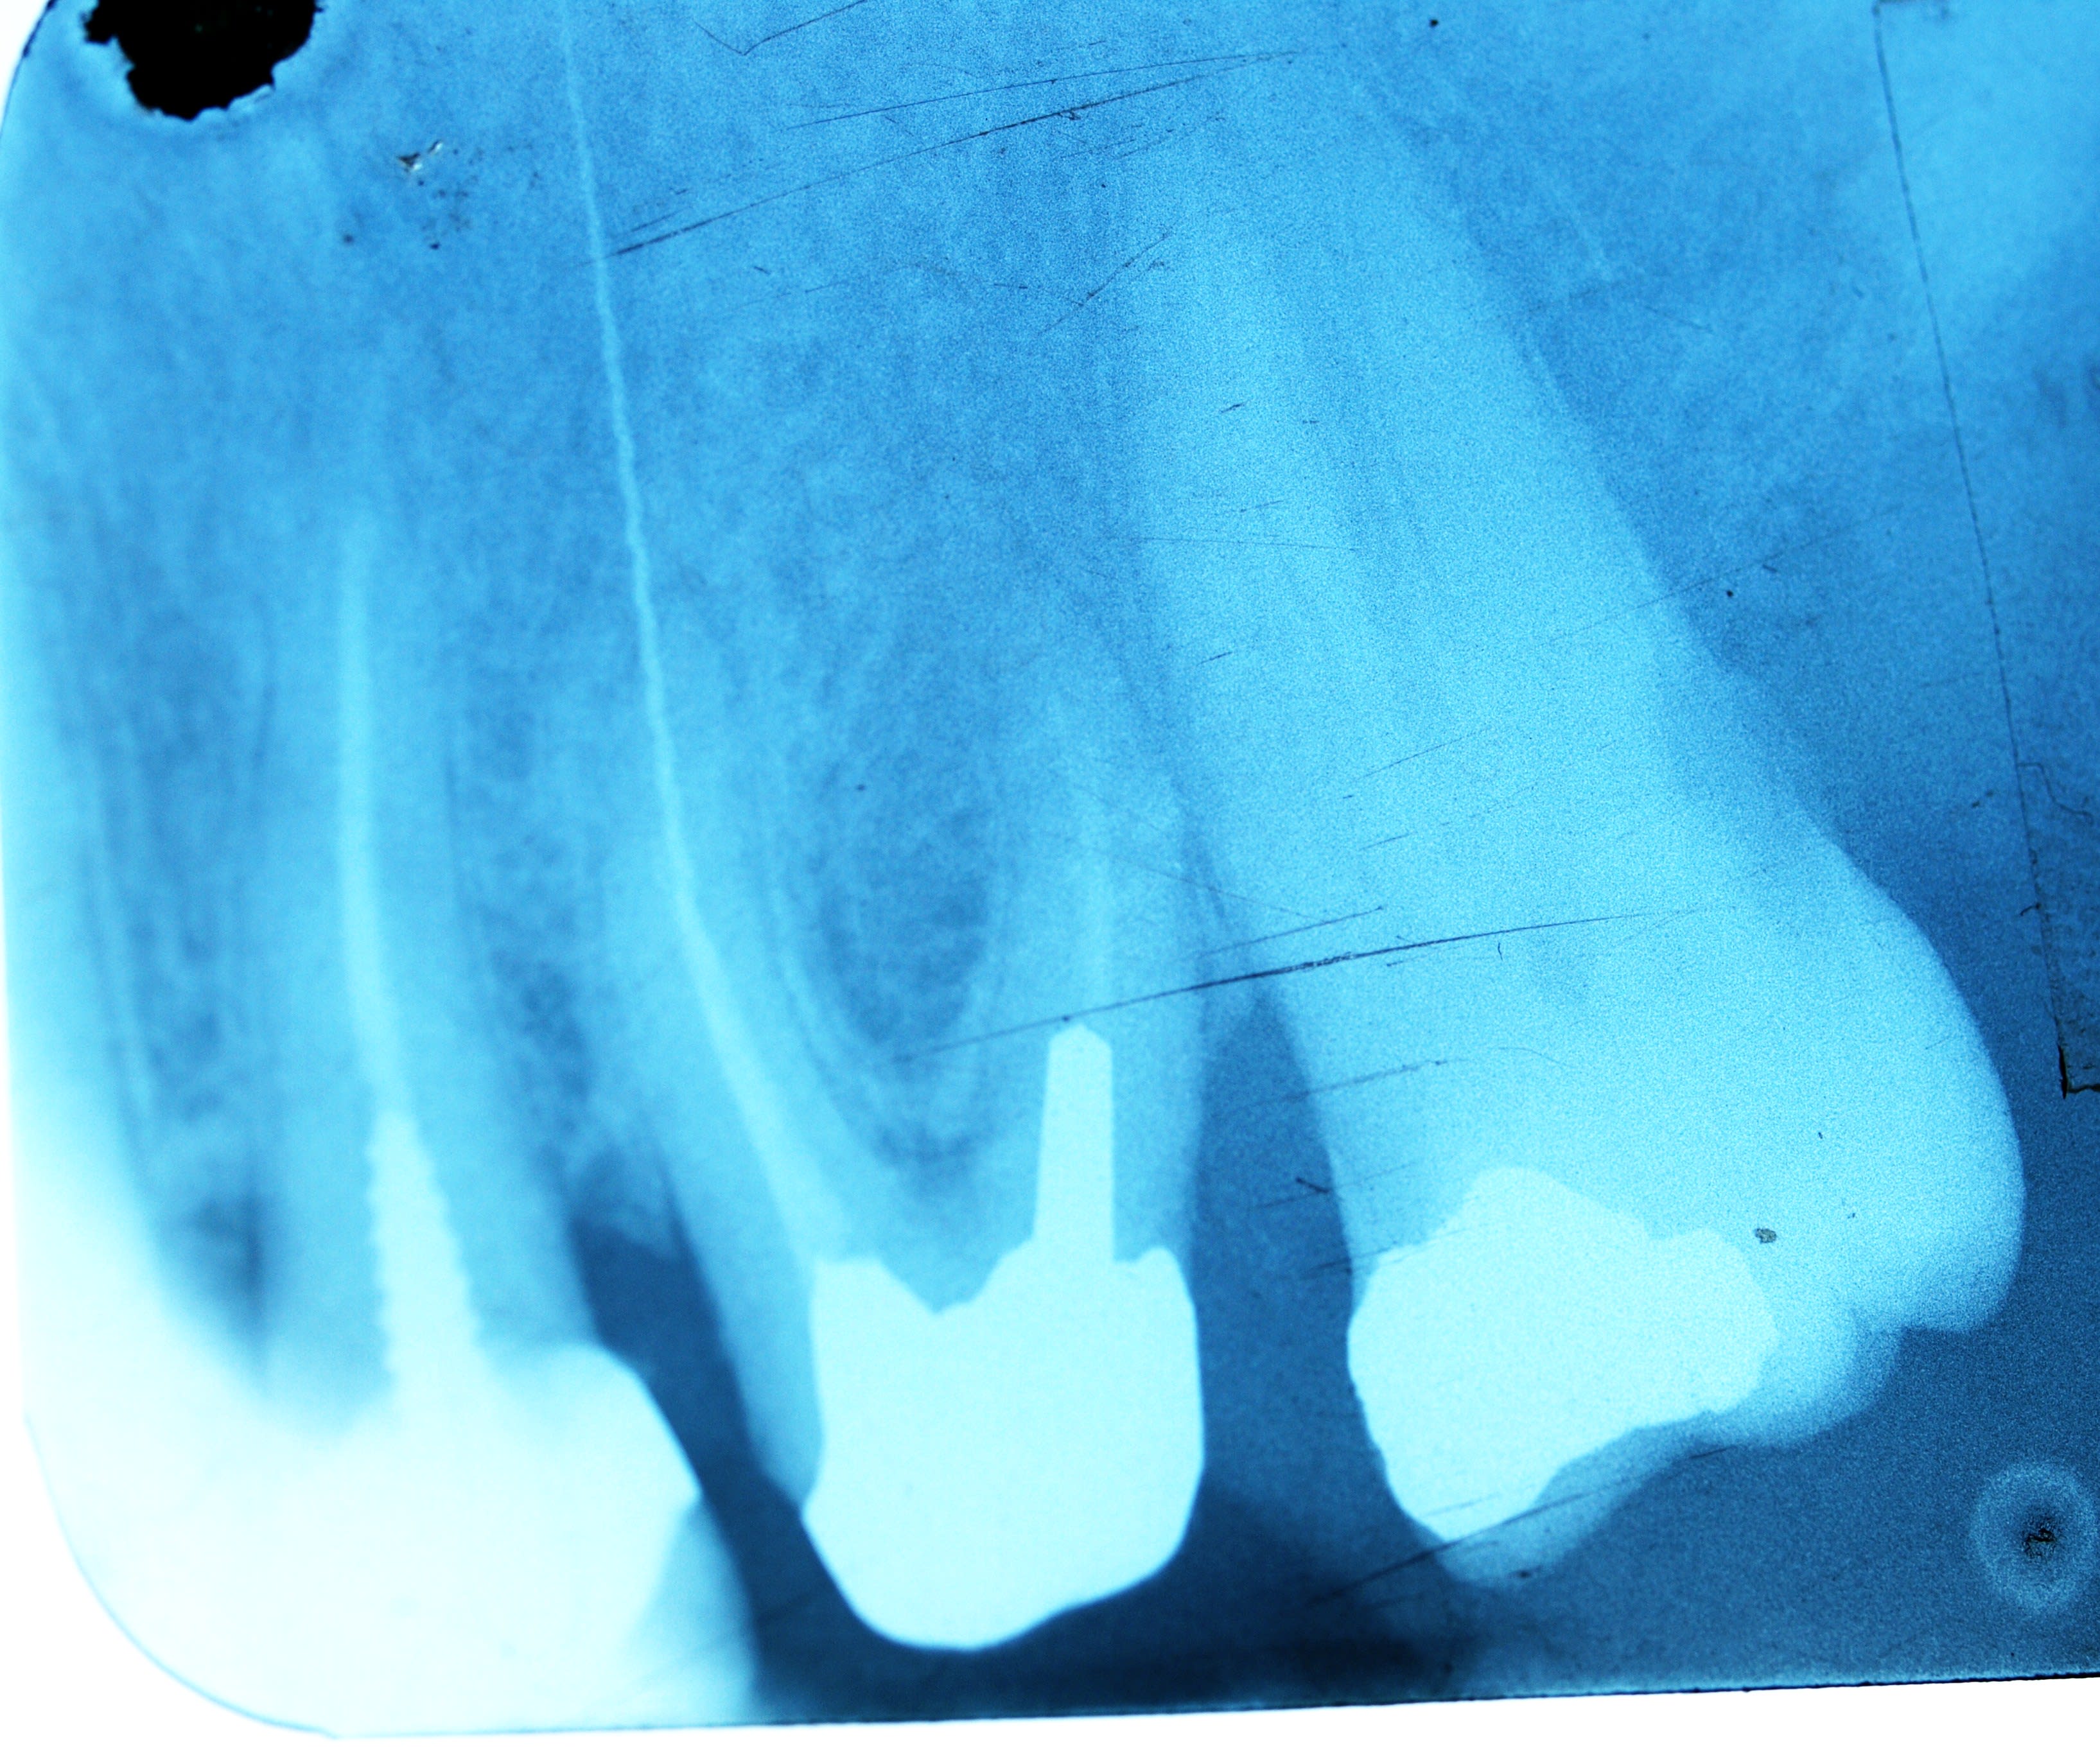

Ben fallait que je me tape le mv2 et puis le D qui était assez courbé au 1/3 (Ca se voit pas trop sur la radio) donc j'ai pas eu le temps. Dès fois faut savoir ne pas avoir les yeux plus gros que le ventre 😉. Donc la 7 c'est pour plus tard

painturlurage apical, chez les nauséeux l'argentique c'est pas mal, moins encombrant qu'un capteur, faut que je m'achète un pspix rapport à l'encombrement.